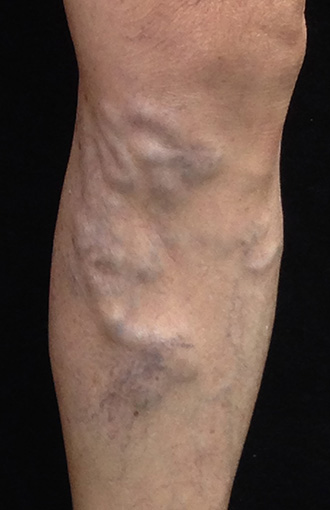

網狀靜脈擴張

血管稍微凸出,不規則彎曲,顏色稍呈藍色,直徑小於0.3公分,常出現在腳後彎及大腿外側,和蜘蛛絲般的細小血管相連。有時會連到深層的靜脈血管,影響血液循環。

大腿外及膝部附近的藍色網狀靜脈,在皮膚白皙的患者可以很清楚的看出走向,,我們稱之為「外側皮下靜脈系統」。這種腿部網狀靜脈擴張和蜘蛛絲會隨著年齡越來越多,或是生完小孩後來逐漸浮現出來,推測可能跟女性荷爾蒙、血管的老化、小靜脈瓣膜退化有關。

這些網狀靜脈擴張由於細小,通常不會影響血液循環,絕大多數來治療的的女性患者,是因為美觀的原因來求診,希望能夠再穿上俏麗的短褲、短裙。另有三分之一左右的病患,是因為局部腫脹、痠痛疲勞前來門診尋求治療,需要仔細觀察,必要時進行血管超音波,來檢查是否潛在有蚯蚓般的靜脈曲張。